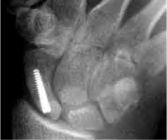

Scaphoid with Acutrak screw

Published November 19, 2013 at 426 × 358 in Scaphoid Fracture